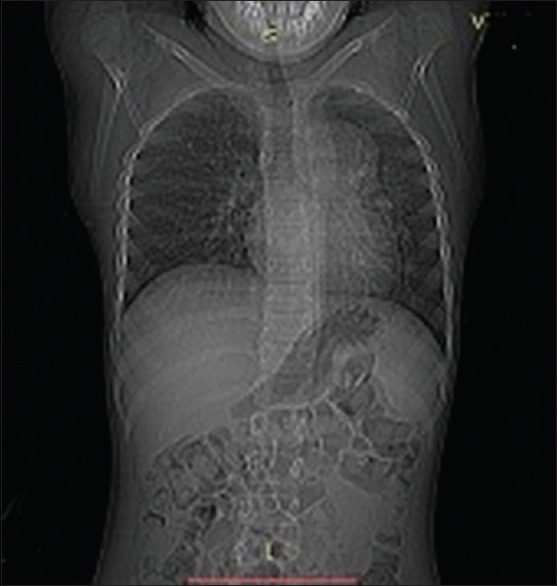

Her investigation yielded hemoglobin was 4 gm% with normocytic normochromic type of anemia, an erythrocyte sedimentation rate of 20 mm at end of 1t hour. Her total leukocyte count and differential leukocyte count were within normal limits, while her tuberculin test was negative. Chest radiograph was suggestive of well-circumscribed mass on upper left side with infective changes [Figure 1]. High-resolution computed tomography (CT) thorax revealed infective changes in both lung fields with well-circumscribed mass of size 4 cm × 4 cm × 4 cm on the left main bronchus and extending on lingual lobe suggestive of thymolipoma [Figure 2]. CT-guided fine-needle aspiration cytology shows fat cells. Intraoperatively, there was a mass of size 4 cm × 4 cm × 4 cm in the anterior mediastinum and communicating with left main bronchus and lingual lobe with cheesy puttaceous material coming out of it and adhere to aorta, pericardium, and pleura. Mass was excised, and partial lobectomy was done. Histopathologically, on cut surface, mass was solid grayish white in color with many cysts of size 1 cm × 1 cm × 1 cm filled with brownish friable material and yellowish fatty area. On microscopy, elements of all three germ layer namely epidermis, skin adnexal structure, adipose tissues in sheets and groups, mature cartilage, muscle tissues, and respiratory epithelium suggestive of mature teratoma were seen [Figures [Figures33 and and44].

| Figure 1:Chest radiograph shows well-circumscribed mass in mediastinum